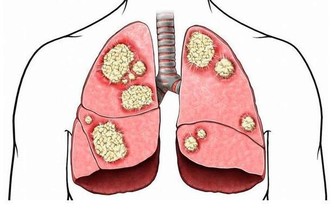

消化道出血或惡性腫瘤:消化道出血時,血液在患者的腸道中聚集。胃酸及腸道細菌將血液分解後,排出的屁有腥臭味。患腸道惡性腫瘤時,癌組織糜爛、出血,再加上細菌的分解發酵作用,也會使放出的屁有腥臭味。

腸道細菌感染:腸道內的細菌毒素通常可使腸黏膜遭到破壞,黏膜上皮細胞壞死並脫落,經過發酵之後,這些物質可產生惡臭氣體,並隨屁一起排出。

若屁奇臭難聞,可能有消化道出血、菌痢、阿米巴痢疾、潰瘍性結腸炎、出血性小腸炎等炎症。此外,惡性腫瘤晚期,因癌腫組織糜爛,蛋白質腐敗,由於細菌的作用,放出的屁也會很臭。愛放屁且經常放臭屁的人就有可能患上大腸疾病,這時你就需要前去診斷了。

如果消化道出血時, 血液在腸腔內滯積, 或腸道發生炎症、潰瘍時, 排出的氣體往往比較腥臭,最好找醫生進行診治,這可能是罹患胃腸道腫瘤的警訊。當患有腸道惡性腫瘤時, 由於癌腫組織糜爛,, 蛋白質腐敗, 經肛門排出的氣體也可出現腐肉樣奇臭。